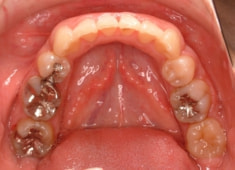

治療後(3年2ヶ月後)